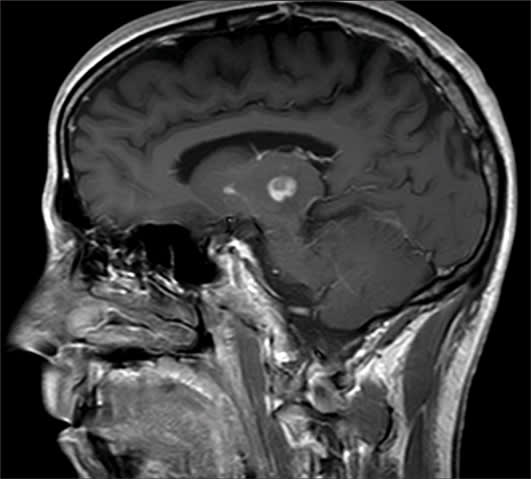

The patient was started on oral pyrimethamine (75 mg daily), sulfadiazine (1 g 4 times daily), folinic acid (20 mg daily), and topical prednisolone acetate 1% eyedrops 2 times daily. Highly active antiretroviral treatment (HAART) was initiated with tenofovir (Viread, Gilead Sciences), emtricitabine (Emtriva, Gilead Sciences), and efavirenz (Sustiva, DuPont). After 2 months of HAART, CD4 count increased to 117 cells/mm3 and viral load decreased to undetectable levels. The patient's right macular and left thalamic lesions showed marked improvement (Figures 4 and 5), but visual loss persisted.

Figure 5. Magnetic resonance image of the brain after systemic therapy showing partial resolution of the left thalamic lesion.

The differential diagnosis of necrotizing retinitis in patients with AIDS includes: toxoplasmosis, cytomegalovirus retinitis, acute retinal necrosis, progressive outer retinal necrosis, and endogenous fungal endophthalmitis. Neuroimaging of our patient revealed the classic asymmetric "target" sign, which helped to confirm our diagnosis of ocular toxoplasmosis. A diagnosis of toxoplasmosis was further supported by reduction in the size of the patient's retinal and cerebral lesions, as well as resolution of his intraocular inflammation with antiparasitic drug therapy.